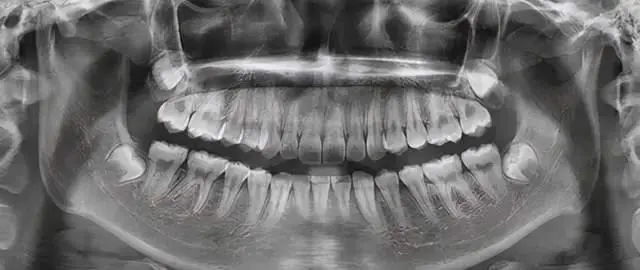

为什么根管治疗需要拍多张牙片?

根管治疗时,拍牙片是很有必要的,并且至少要保证3张牙片。

第一张在治疗前,帮助医生了解牙根的基本情况,制定治疗计划;

第二张在治疗中,帮助医生了解治疗情况,如根管预备是否到位等,并制定下一步治疗方案;

第三张是在治疗结束后,帮助判定根管充填质量,发现问题及时补救。